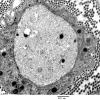

PERIPHERAL NEUROPATHY

18 HEREDITARY DISORDERS

Charcot-Marie-Tooth 1 (CMT-1) (6)